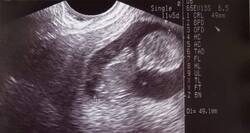

The practice of examining pregnant women using ultrasound is called obstetric sonography, and is widely used. In physics, 'ultrasound' refers to sound waves with a frequency too high for humans to hear. The sound reflects and echoes off parts of the tissue; this echo is recorded and displayed as an image to the operator.

in your prenatal stage, your doctor will talk about various diagnostic check-ups to ensure the status of your health and that of your unborn baby. One important reason is to check for a chromosomal abnormality like Down syndrome.